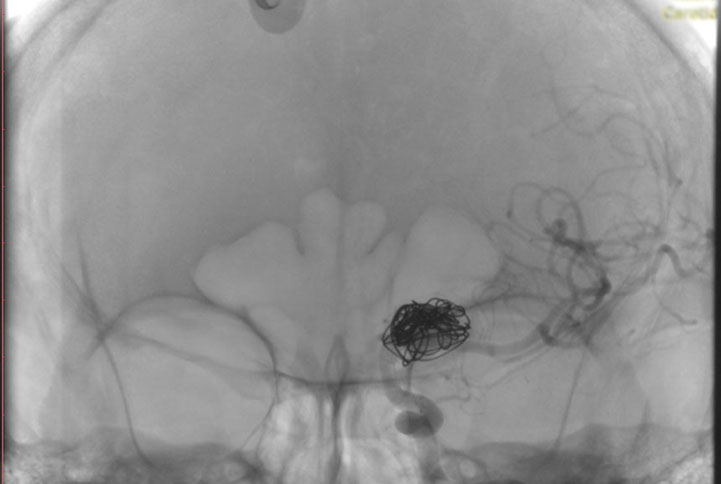

La paciente ingreso al Servicio de Hemodinamia el día martes 11 de febrero con un aneurisma cerebral gigante en la carótida izquierda y se le practicó una embolización; es decir una oclusión por dentro del mismo, donde se colocó un dispositivo denominado coils más un stent diversor de flujo. El procedimiento fue exitoso y contó con la colaboración de médicos neurointervencionistas del Instituto Oulton de la Ciudad de Córdoba.